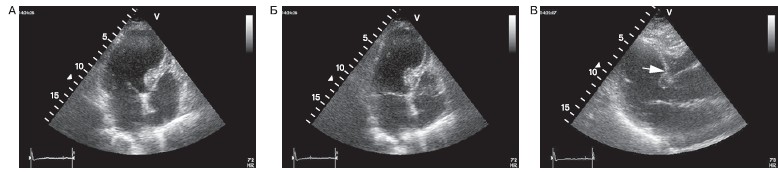

Истинные аневризмы обычно формируются после крупноочаговых ИМ при окклюзии передней нисходящей артерии с большой зоной инфаркта. Характерным признаком истинных аневризм являются диастолическая деформация полости желудочка и истончение его стенки (рис. 7).

Рисунок 7. Аневризма верхушки левого желудочка с деформацией полости левого желудочка и истончением стенки аневризмы.

А — верхушечный доступ, позиция 4 камер в диастолу; Б — верхушечный доступ, позиция 4 камер в систолу; В — парастернальный доступ, данная ось левого желудочка; истончение стенки в области межжелудочковой перегородки (стрелка).

Дискинезия нередко наблюдается в зоне аневризмы, но она не является характерным признаком аневризмы. В отличие от аневризмы дискинезия представляет собой систолический феномен.